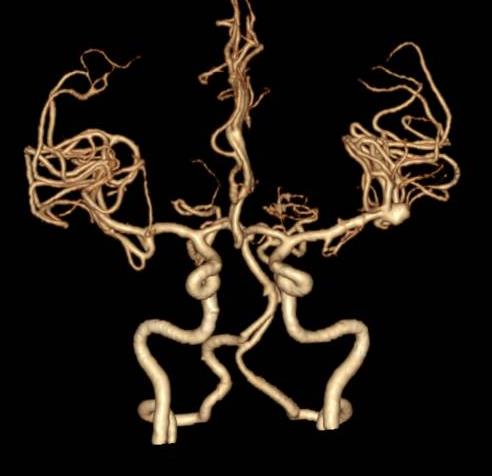

颅脑CTA示左侧大脑中动脉分叉处动脉瘤